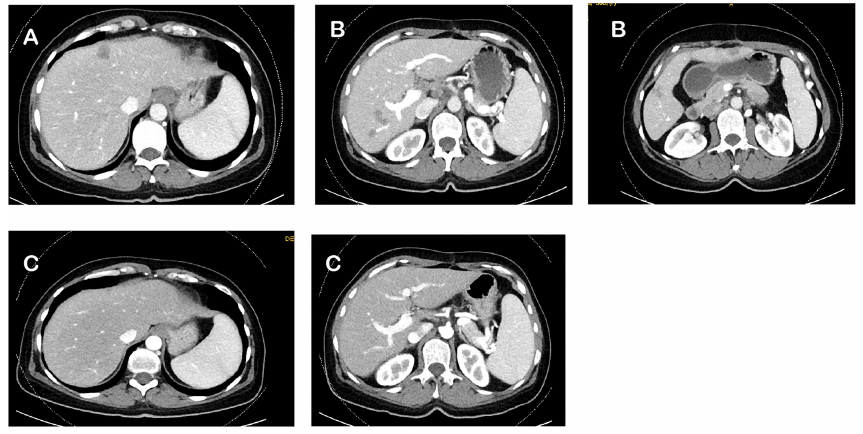

圖 1 患者治療過(guò)程中 CT 變化:(A) 2017 年 2 月基線 CT;(B) 2017 年 6 月 CAPOX 輔助化療后的 CT;(C) 2018 年 10 月,達(dá)拉非尼+曲美替尼+西妥昔單抗治療 1 年后的 CT

術(shù)后計(jì)劃予 6 個(gè)月的卡培他濱聯(lián)合奧沙利鉑 (CAPOX) 輔助化療。然而,在 CAPOX 方案輔助化療 3 個(gè)月后,2017 年 6 月 CT 顯示肝臟新發(fā) 5 個(gè)轉(zhuǎn)移灶,腫瘤標(biāo)志物癌胚抗原 (CEA) 升高;

2017 年 6 月至 9 月,患者接受 FOLFIRI 聯(lián)合貝伐單抗一線姑息治療,治療 3 月后 CT 顯示肝臟轉(zhuǎn)移灶較前進(jìn)展,伴 CEA 持續(xù)升高;

因肝轉(zhuǎn)移灶無(wú)法切除,患者入組 BEACON 臨床試驗(yàn),接受 FOLFIRI 聯(lián)合西妥昔單抗治療 2 個(gè)月,2017 年 11 月 CT 顯示肝轉(zhuǎn)移灶繼續(xù)進(jìn)展,伴新發(fā)肺轉(zhuǎn)移及腹膜后淋巴結(jié)轉(zhuǎn)移,CEA 繼續(xù)升高;患者退出 BEACON 臨床試驗(yàn);

2017 年 12 月,由于無(wú)藥可用,患者開(kāi)始嘗試超適應(yīng)癥用藥,即達(dá)拉非尼+曲美替尼+西妥昔單抗三藥聯(lián)合治療,治療 2 月后 CT 顯示肝、肺及腹膜后淋巴結(jié)部分緩解;繼續(xù)治療 2 月后肝、肺及腹膜后淋巴結(jié)轉(zhuǎn)移幾乎完全消失;2018 年 8 月,CT 顯示病情穩(wěn)定;2018 年 10 月,PET/CT 顯示完全緩解;